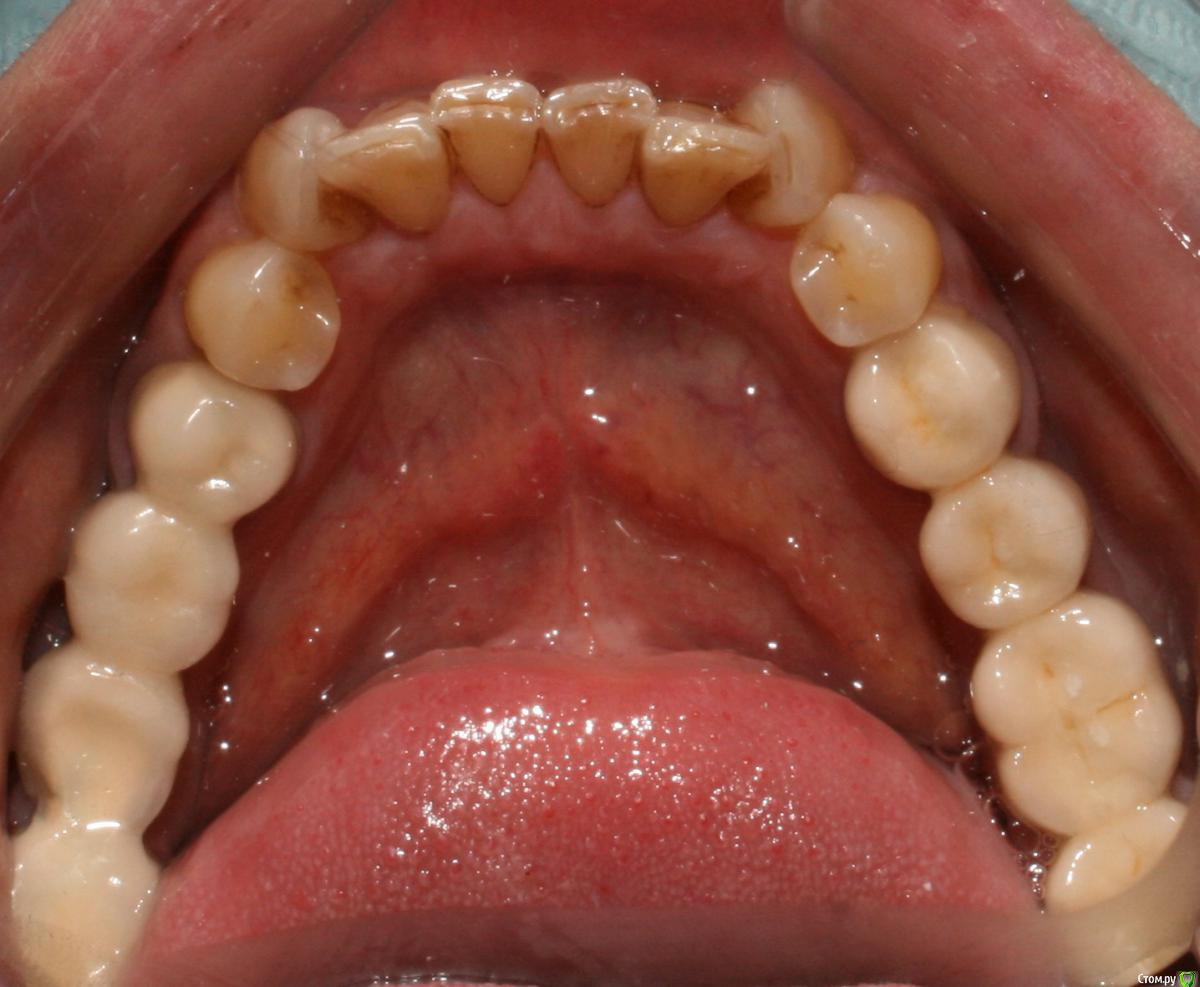

kramer Опубликовано 17 января, 2018 Поделиться Опубликовано 17 января, 2018 (изменено) Коллеги, добрый вечер. Помогите начинающему ортопеду. Заранее прошу простить за качество фото. Пациентка обратилась с целью улучшения эстетики фронтальных зубов. Около года назад один врач из нашей клиники делал м/к на боковые зубы (пациентку устраивают), при этом, по всей видимости, было снижение прикуса из-за стирания, но его высоту не восстанавливали. Теперь настало время передних зубов, и работать, получается, придется с имеющейся высотой. План лечения: 14, 24 - м/к, 13-23 имакс коронки/виниры. Меня смущают фасетки стираемости на клыках в/ч. Вопрос: каким образом лучше их реставрировать во избежание сколов реставраций? Делать полные коронки? Спасибо, надеюсь на ваш совет. Изменено 17 января, 2018 пользователем kramer Ссылка на комментарий

kramer Опубликовано 21 января, 2018 Автор Поделиться Опубликовано 21 января, 2018 Сама судьба толкает к тоталу. Техник пробовал восковать в таком прикусе - не получается, мешают нижние клыки, да и перекрытие какое-то некрасивое получается, глубокое Ссылка на комментарий

kramer Опубликовано 21 января, 2018 Автор Поделиться Опубликовано 21 января, 2018 Но даже в случае тотала, непонятно, что делать с 43 и 33 из-за их положения. Ссылка на комментарий

kramer Опубликовано 22 января, 2018 Автор Поделиться Опубликовано 22 января, 2018 Я не пойму,почему все в один голос твердят,что здесь нужно поднимать прикус?Какие показания? С чего вы это решили?Нужно исходить из возраста пациента. Да здесь видны фасетки стираемости,но не стоит забывать,что есть еще компенсация стираемости в виде роста альвеолярного отростка с зубами (гипертрофия) и далеко не всегда стираемость приводит к снижению МАВ. Здесь как раз намного важнее определиться с ЦС и ВНЧС,как минимум провести тесты,сделать КТ сустава.Если все в норме,то нет нужны поднимать высоту. Я думаю в данной клинической ситуации возможно отмоделировать достточно неплохо фронт,хотелось бы увидеть ваш вариант воска. Вот воск. С нижних клыков убрано по 1-1,5 мм примерно Ссылка на комментарий